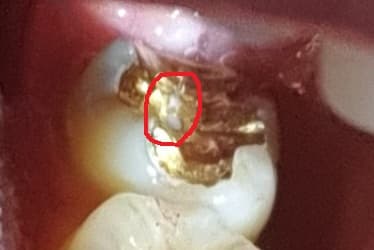

어금니 골드 인레이가 1년 안되고 떨어져서 재부착했는데 좀 불편 하다고하니 저렇게 교정해주신다고 뚫어주셨는데 안에 치아가 보이네요

교합면이라 좀 불안하기도해서 다양한 전문의분들의 고견을 듣고 싶습니다

보철물이 얇거나 해서 구멍이 났다면 일반적으로는 보철물을 교체해 주는것이 좋습니다.

내부로 추ㅇ치가 생길수 있고 잘 탈락할수 있기 때문이에요.

교합면에서 치아가 보일정도면 다시 치료를 하셔야될 가능성이 높아 보입니다. 치과에 가셔서 검진후 치료 상담을 받아보세요.

교합면에 구멍이 있더라도 문제가 안되는경우가 많지만 걱정되시면 새로 하시는것도 좋습니다